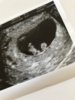

Vis vedlegget 258222

Mente den e

jubler også for kjempe vonde pupper og en kvalme som gjør at jeg ikke helt vet hvor jeg skal gjøre av meg